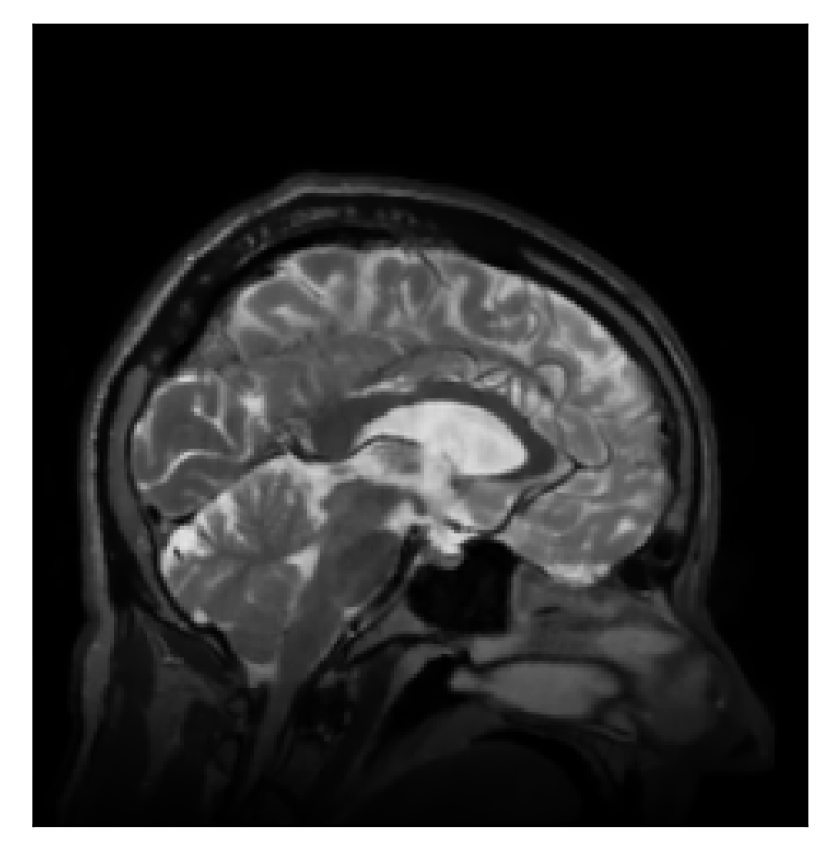

The second experiment is set up similarly to the previous one. We asked volunteer 3 to change position only once during the acquisition phase. We consider, now, a corrupted T2-FLAIR-weighted contrast with a reference T1-weighted contrast (see Table 1). The most important difference with the previous experiment, besides the type of contrast pair considered, is related to the randomized acquisition protocol. In this case, the scanner reconstruction employs a compressed-sensing reconstruction, and is not suited as input for the proposed motion-correction algorithm (see Appendix A). Therefore, for adequate motion correction, we must set up an intermediate step for processing the raw -space data via the SENSE reconstruction.

We further discuss the results of this experiment in Section 4.3.

4.3 Experiment 3: scanner reconstruction vs raw k-space data

The results of the two experiments described in Section 3.3 are depicted in Figures 12 and 14. The main difference between the two experiments is related to the input data for the proposed motion-correction algorithm.

In the case of randomized sampling, the scanner reconstruction is not adequate as input data for the proposed motion-correction algorithm, because it employs a compressed-sensing algorithm. We speculate that compressed-sensing reconstructions degrade the information contained in the corrupted volume, and the corrected contrast cannot be effectively recovered by simply removing rigid-motion artifacts (we defer the degraded results when using scanner reconstruction data in Appendix A). However, when the input data is obtained by directly processing the raw -space data via the SENSE reconstruction, the motion-correction scheme is able to successfully remove the motion artifacts (Figure 14).

| Section 3.3, Figure 14 | Sagittal | 24.72 | 28.76 | 0.6762 | 0.7818 |

| Coronal | 25.95 | 29.54 | 0.7238 | 0.8107 | |

| Axial | 25.08 | 29.59 | 0.7263 | 0.8407 | |

| Section 3.3, Figure 14 | T2-FLAIR | Completely corrected | Some blurring | No additional artifacts | Good grey white matter differentiation |